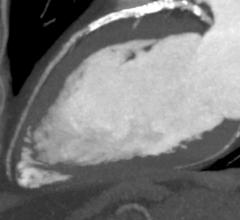

With headquarters in Tustin, Calif., Canon Medical Systems USA Inc. markets, sells, distributes and services radiology and cardiovascular systems, and coordinates clinical diagnostic imaging research for all modalities in the United States. Canon Medical Systems Corporation, an independent group company of Canon Inc., is a global leading provider of diagnostic imaging systems including CT, MRI, Ultrasound, X-ray systems and clinical laboratory systems. In business for more than 100 years, Canon Medical Systems Corporation (formerly Toshiba Medical Systems Corp.) was built to improve the quality of life for all people. It delivered on this mission with medical innovations that are “Made for Life”—made to improve the lives of patients, clinicians and administrators. Its legacy was built with pioneering medical technology, such as the world's first X-ray machines in 1932 and Japan's first magnetic resonance imaging (MRI) systems in 1983. Canon Inc. entered the healthcare business in 1940 with the development of Japan’s first indirect X-ray camera which was used for the early detection of pulmonary tuberculosis. The partnership of Toshiba Medical Systems Corporation and Canon (now Canon Medical Systems Corp.) brings together two cutting-edge technology businesses, founded with similar values of creativity, flexibility and patient-friendly healthcare solutions. Today, their combined history of research and innovation drive forward Canon Medical Systems’ vision for building a world-class healthcare enterprise. For more information: https://us.medical.canon/

Canon Medical Systems’ offering includes: computed tomography, magnetic resonance, ultrasound, X-ray, cath and EP lab